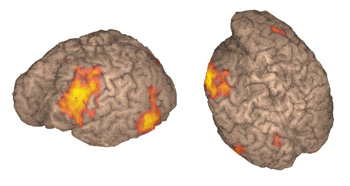

Right hemisphere in 3D-surface rendition

Right handed 15 year-old-boy with intractable epilepsy performing a verbal "repetition task." The surface rendition beautifully depicts the activation occurring in the posterior third of the right superior temporal gyrus and extending toward supramarginal gyrus and Brodmann's area 7. The areas of activation are better displayed than with conventional 2D MR images.